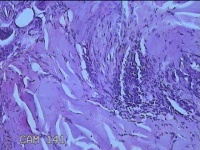

性别

男

年龄

41岁

临床诊断

皮脂腺痣

一般病史

双下肢红斑痒一年余。

标本名称

双下肢肿物

大体所见

灰白暗红色肿物0.8x07x0.3cm一个,表面糜烂。